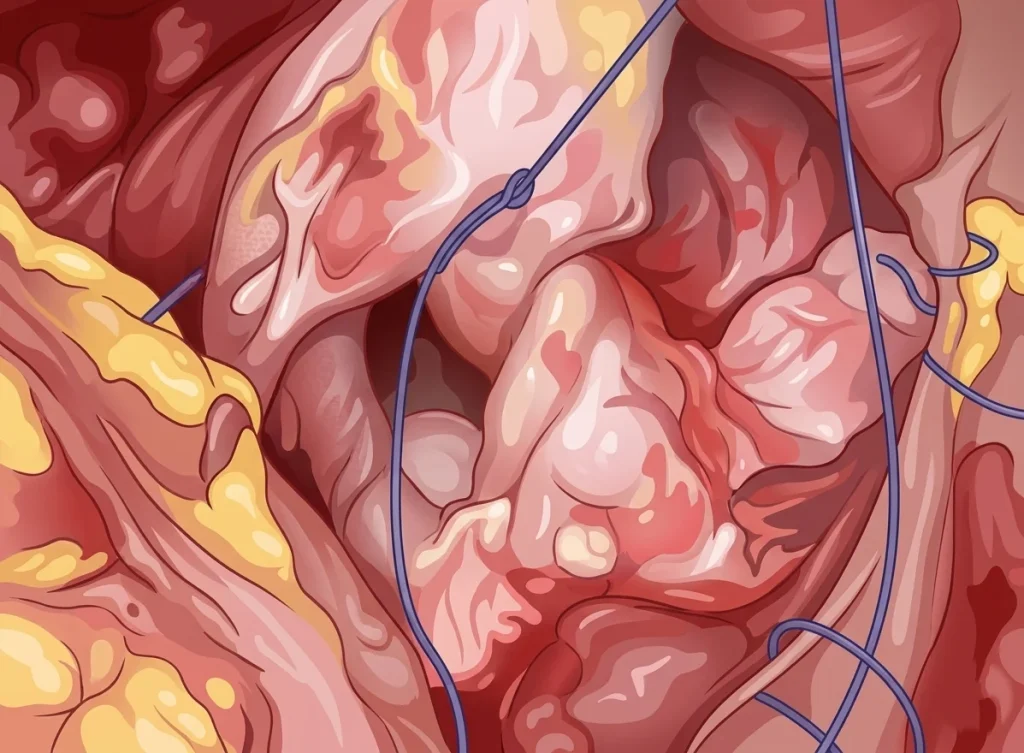

Παρακάτω παραθέτουμε εικόνες από λαπαροσκοπικό χειρουργείο μας. Τα χειρουργικά στάδια είναι η εκτομή του συριγγίου, η συρραφή του κόλπου και της ουροδόχου κύστης και η τοποθέτηση εντερικού λίπους (επίπλουν) μεταξύ κόλπου και κύστης για την καλύτερη επούλωση και μείωση των υποτροπών.